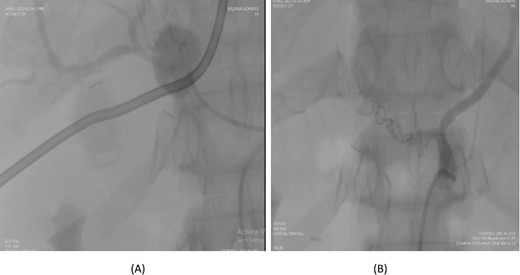

A 57-year-old female underwent a distal pancreatectomy for a pancreatic neuroendocrine tumo. On the 13th postoperative day, the patient presented in a state of shock and intraperitoneal bleeding. A contrast-enhanced CT angiogram revealed the presence of a pseudoaneurysm originating from the splenic artery. The patient underwent endovascular coil embolization of the splenic artery and bleeding stopped and was discharged 3 days following the procedure (Fig. 1).

Case 1. (A) Angiogram pseudoaneurysm from splenic artery. (B) Angioembolization of splenic artery with coil